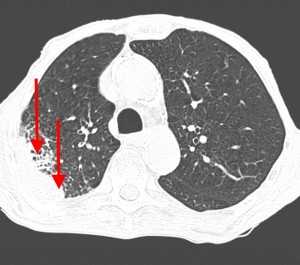

Метастазы в легких на КТ

Гематогенные метастатические узлы в легких на КТ имеют довольно четко очерченные и ровные контуры. Нечеткие, расплывчатые или лучистые контуры наблюдаются в том случае, если есть инвазивный рост в окружающую легочную ткань. Локализуются преимущественно в нижних, периферических отделах легких, хаотично, без очевидной связи с бронхами и крупными легочными сосудами.

Часто на КТ-сканах визуализируется характерная дорожка к корню легкого. В динамическом наблюдении отмечается инфильтративный рост опухоли.

Вторичные узлы гематогенного характера чаще всего имеют ровные края, четкие контуры и однородную структуру. Возможны изменения структуры опухоли вследствие кровоизлияния в паренхиму, обызвествлений, некроза центральной части узла, а также рубцов. Края узла могут стать нечеткими, расплывчатыми, если опухоль провоцирует отек легочной паренхимы, либо «лучистыми», если имеет место опухолевый лимфангиит.

Гематогенные метастазы наиболее часто локализуются в периферических отделах легких, вдали от крупных сосудисто-бронхиальных пучков, вблизи плевральной оболочки. При множественных поражениях гематогенного характера наблюдается тенденция к увеличению количества очагов в направлении «сверху-вниз». Чаще гематогенные метастазы расположены хаотично, вне четкой связи с бронхами и видимыми легочными сосудами. Практически не бывает такого, чтобы гематогенные вторичные узлы находились только с одной стороны, или занимали только одну долю или сегмент. При наличии такого распределения в первую очередь нужно думать о туберкулезе (верхние доли), множественных абсцессах и т. д.